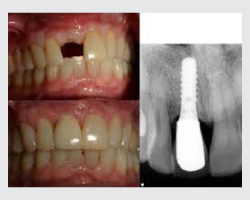

Dental implants are artificial tooth roots made of medical-grade titanium that are surgically placed into the jawbone. Once the implant integrates with the bone, a crown is fixed on top, giving you a strong, natural-looking replacement tooth.